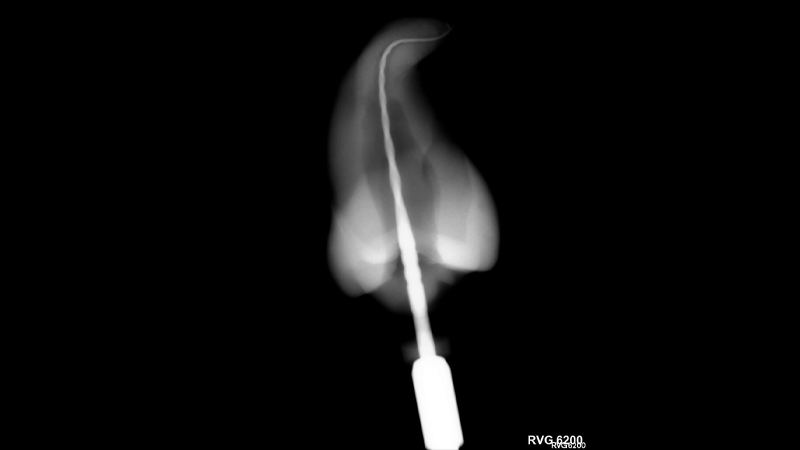

Reciproc blue: Is a one file endodontic procedure the new reality?

The goal of endodontics is to remove a multispecies biofilm from the root canal system to treat apical periodontitis. Historically this was done with a series of hand files that were prone to procedural mishaps, inefficient, and potentially more problematic for patients.1,2 An obvious way to eliminate the potential for iatrogenic issues with hand files is … Read more